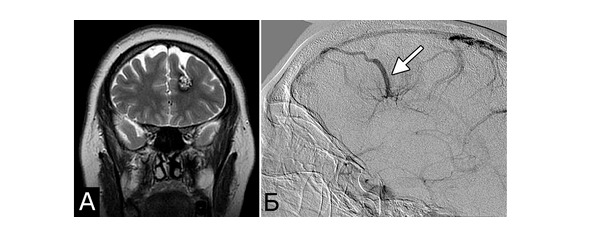

Сочетание каверномы с АВМ выявлено у двух больных, причем в обоих случаях клинические проявления заболевания были обусловлены АВМ, а кавернома явилась случайной находкой (рис. 1).

Рис. 1. Б-ная Г., 27 лет. Сочетанная сосудистая патология мозга: КМ передне-медиальных отделов височной доли справа (А – МРТ, режим Т1; Б – МРТ, режим Т2); АВМ медиальных отделов лобно-теменной области справа (В – МРТ, режим Т2; Г – МРТ-АГ). Клиническое течение: редкие вторично-генерализованные судорожные эпилептические припадки, начинающиеся с судорог в левых конечностях